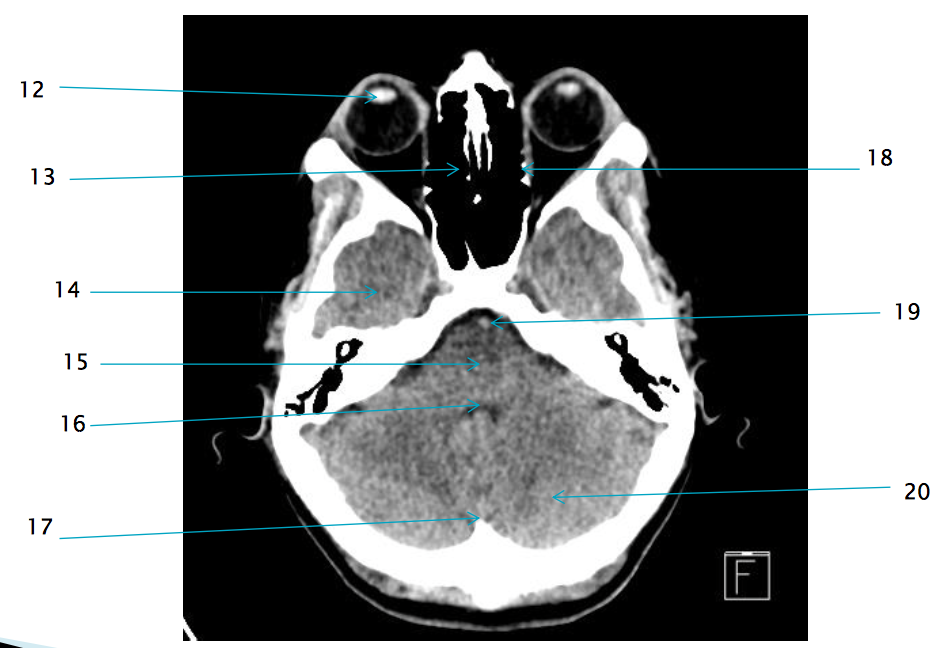

14

R temporal lobe

12

lens of R eye

13

ethmoid air cells R

21

R zygomatic bone

17

internal occipital protuberance

19

basilar artery